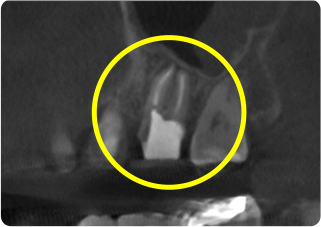

精密根管治療③

術前

術後

| 主訴 | 奥歯で噛むと痛い |

|---|---|

| 治療期間/回数 | 1ヵ月、4回 |

| 価格(税込) | 88,000円(税込) |

| リスク・副作用 | 病変再発、歯根破折の可能性 |

| ポイント | う蝕検知液を用い、むし歯の取り残しが無いようにし、ラバーダム防湿を行い、無菌的に根管治療を行った。根管充填材は、殺菌作用の強い保険適応外のMTAセメントを使用した。 |